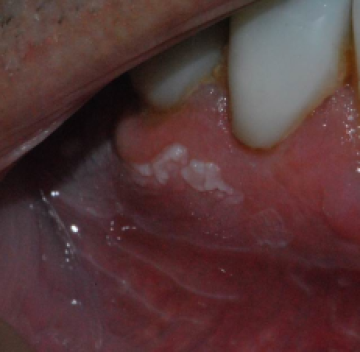

Een 70-jarige man presenteert zich met een witte vlek onder op het tandvlees.

Hij heeft geen pijn, maar de vlek is ook niet weg te poetsen. Wat is uw diagnose?